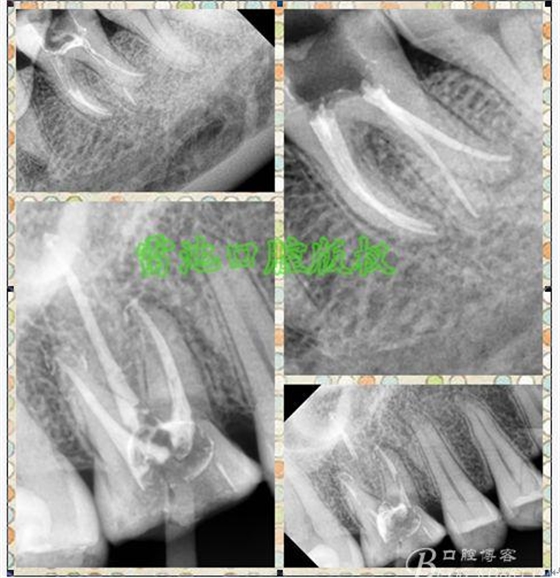

E、X線影像學的檢查研判能力:這點不需要強調(diào)太多,對于普通的非CBCT的二維影像對醫(yī)生讀片能力有一定的要求,有個逐步提高的過程,非一蹴而就,需要學會把二維的X線影像與三維的解剖結(jié)構(gòu)進行良好的對應結(jié)合,對于某些鈣化的髓室底,應通過想象把根管口的分布、根管的走向以及各種變化通過想象投射到對應的髓室底上;

1、查閱各種文獻,MB2的發(fā)生率在52-96%之間,治療時遺漏是上頜磨牙根管治療失敗的主因,2、一般位于MB1根管口與腭根管口方向的0.5-5mm范圍內(nèi),而大多數(shù)都位于MB舌側(cè)的1-3mm處,其中2mm以內(nèi)占85.7%,3、MB1-P根管口連線與MB1-MB2根管口的連線夾角大部分(74.3%)在30度以內(nèi);4、MB2的尋找大部分需要去除相應部位的牙本質(zhì);5、當找到的MB根管口呈“長線型”且有深色凹線向舌側(cè),或者找到的MB根管口明顯偏頰多提示有MB2的可能;6、DOM(牙科手術(shù)顯微鏡)的使用有助于找尋MB2;